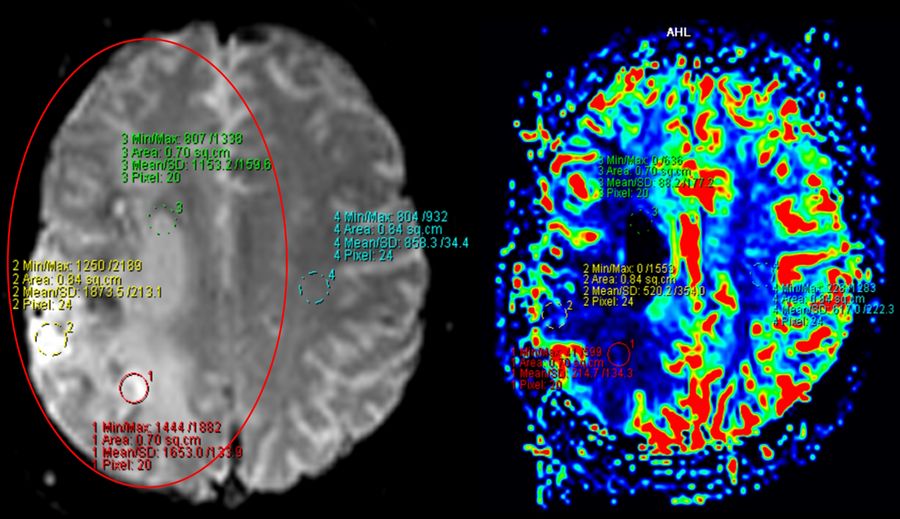

Post-surgery assessment

The postoperative CT scan showed no signs of postoperative complications. The presurgical area of ischemia in the territory the right MCA was also observed. The patient showed no additional postoperative neurological deficits and was discharged three days post-surgery.